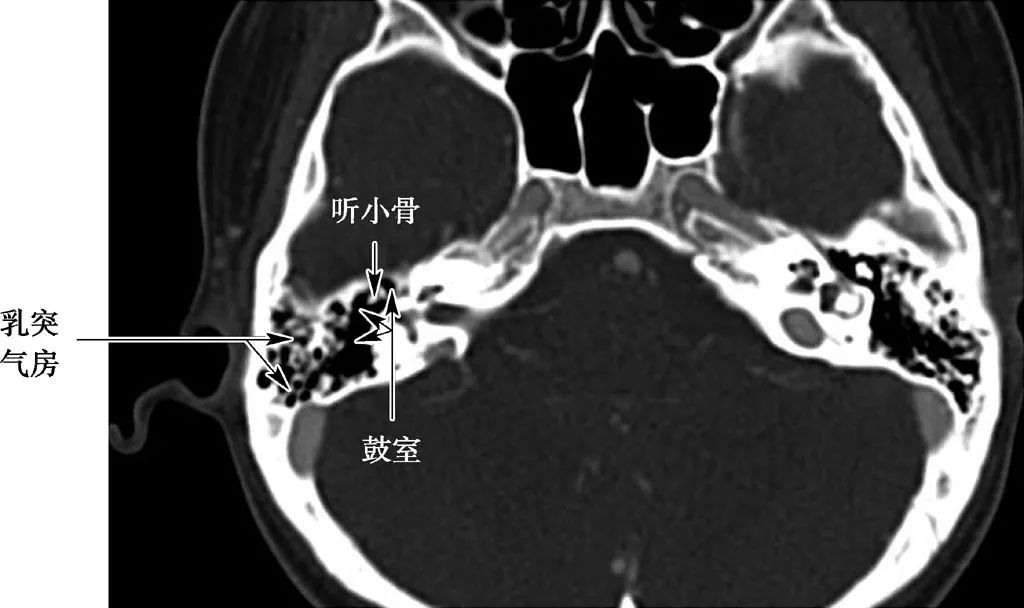

中耳结构

(CT横断面自下至上两个层面)

鼓室内含3块听小骨——锤骨、砧骨、镫骨。

听小骨链

3块听小骨相连接形成听骨链,两端分别连接鼓膜与前庭窗。鼓室周围有6个壁: